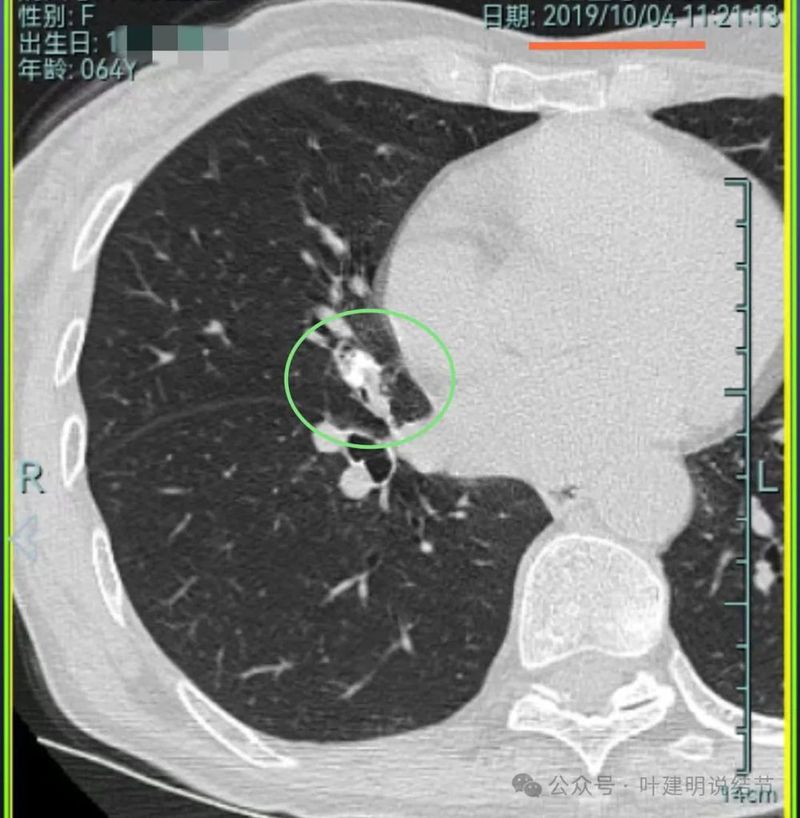

先来看2019年时的影像:

病灶3:右中叶混合密度结节,有分叶征,有收缩力,整体轮廓与边界清。

病灶4:右中叶伴钙化结节,考虑良性。

我想我们这样也来考虑问题:1、左侧已经手术的确诊是肿瘤性质,左上已经消融的也是随访持续存在的磨玻璃密度结节,虽然没有病理依据,仍然要考虑广义上来讲的肿瘤范畴,看了以前的片子,从2019年到2023年并没有显著的进展,大概是肺泡上皮不典型增生可能性大。右侧的也有磨玻璃结节与混合磨玻璃结节考虑是肿瘤范畴的。所以总体上两肺多原发早期以磨玻璃为表现的肺癌,整体风险都不大。2019年切除的左肺下叶病灶也是纯磨玻璃密度,其实如果继续随访或者只做楔形切除也并没有什么关系。这说明体质本身或者致病的因素,就是容易长磨玻璃肺癌的,即便把目前发现的都解决,后续仍可能再有新的。原因不明,致病因素仍在。2、右肺上叶红色之处从2019年开始,是逐渐进展的,当然即便是现在,也不是说危险就已经很大,考虑仍然是原位癌或者微浸润性腺癌可能性大;中叶蓝色这处乍一看像至少是微浸润,但前后对比以后发现从2019年到现在,几乎没有显著进展,这样的话慢性炎伴肺泡上皮增生或者伴纤维增生也是有可能的,至少风险并不能认为大;右肺下叶黄色这一处,使纯磨玻璃密度,整体轮廓与边界清楚,考虑是肿瘤范畴的,不典型增生可能性较大,也有可能原位癌,随访稍有进展,风险仍然不大;中叶绿色这处是慢性炎伴钙化的,靠近叶裂的地方也像慢性炎,但此处随访有所进展。不过因为有卫星灶,整体显得比较散,所以虽然恶性可能性较大,但也不能完全除外炎性的可能性。当然如果此灶确实恶性,那风险则相对较其他进展缓慢的要高一些。从目前右侧所在的这些病灶来讲,真正有一定的风险而且最为确切的是红色这处,而且应该也没有到浸润性腺癌或者说不处理会要转移很危险这种程度。3、明确了多原发早期肺癌没有办法预防与控制,也明白了目前已经存在的较明显的这些病灶总体风险的高低。我们再来考虑需不需要近期干预处理。左侧既手术过又消融过,右侧的多发病灶目前又还没有到危险很高的程度,又没有办法预防后续再有新的病灶。我个人偏保守,我觉得仍然可以半年复查随访,如果最具风险的病灶有进展并且不处理可能导致不良后果,到这样的程度再来考虑综合如何处理干预便可。4、假如右侧我们予以处理,上叶红色的以及中叶蓝色的都可以楔切,但绿色考虑良性的再进展或以后像恶性时怎么办?而若中叶切除加上叶楔切,在左侧已经手术过的情况下肺功能影响相对也不小,何况右下比较中间的位置还有桔色这处呢。当然右下这处得考虑消融。所以,我的想法还是能熬再熬下,待其他监测有变化再通盘考虑。意见供参考!